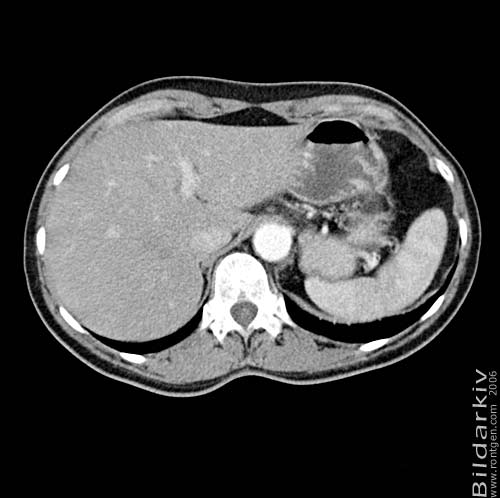

Thorax 53

Snitt över thorax med kontrast. Sk. mediastinum-fönstersättning.

CT Röntgen Helsingborgs lasarett

Mediastinum